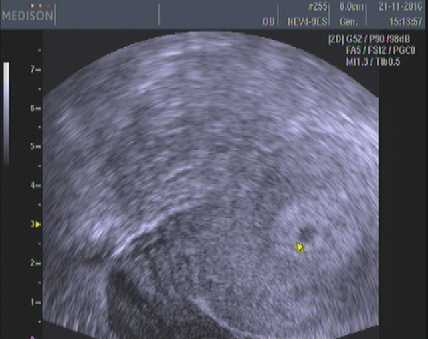

No vidis že tam je, to jsi tak 3-4tt? Gratuluji...

Autor: ÁDA 21.11.2016 v 17:56

[954841]5-6tt

Ten digitál mi minule ukázal 4-5tt těhotná,takže by to odpovídalo

3-4tt?to by viděl max tu sliznici..